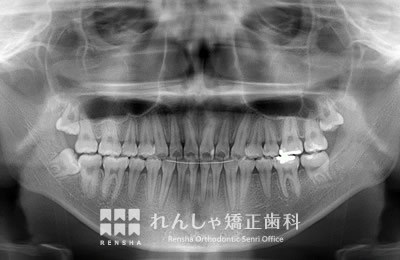

大人

軽度の上顎前突であれば、上奥歯の後方移動で前歯の前突を改善することもありますが、上顎前突は叢生の問題も絡んでいることがほとんどで、永久歯の抜歯が必要になることがあります。また上奥歯の後方移動には矯正矯正用アンカースクリューの併用が効果的です。

治療前

| 主訴 | 出っ歯と前歯のがたつき |

|---|---|

| 診断名 | Angle Class II 上顎前突 |

| 初診時年齢 | 20歳7か月 |

| 装置名 | マルチブラケット装置 矯正用アンカースクリュー |

| 抜歯非抜歯 | 上下顎左右第二小臼歯の抜歯(合計4本) |

| 治療期間 | 3年2か月 |

| 費用の目安 | 約75万円+消費税(検査料金、都度の処置費用等も合わせた総額) |

| リスク副作用 | 歯の移動に伴う軽微な歯根吸収、歯槽骨吸収、歯肉退縮(本症例では軽度の歯肉退縮と歯根吸収を認めた)、矯正器具装着中のカリエスリスク増大(本症例では大臼歯にカリエスが発生し、その後う蝕処置)、上顎左側犬歯の失活 |